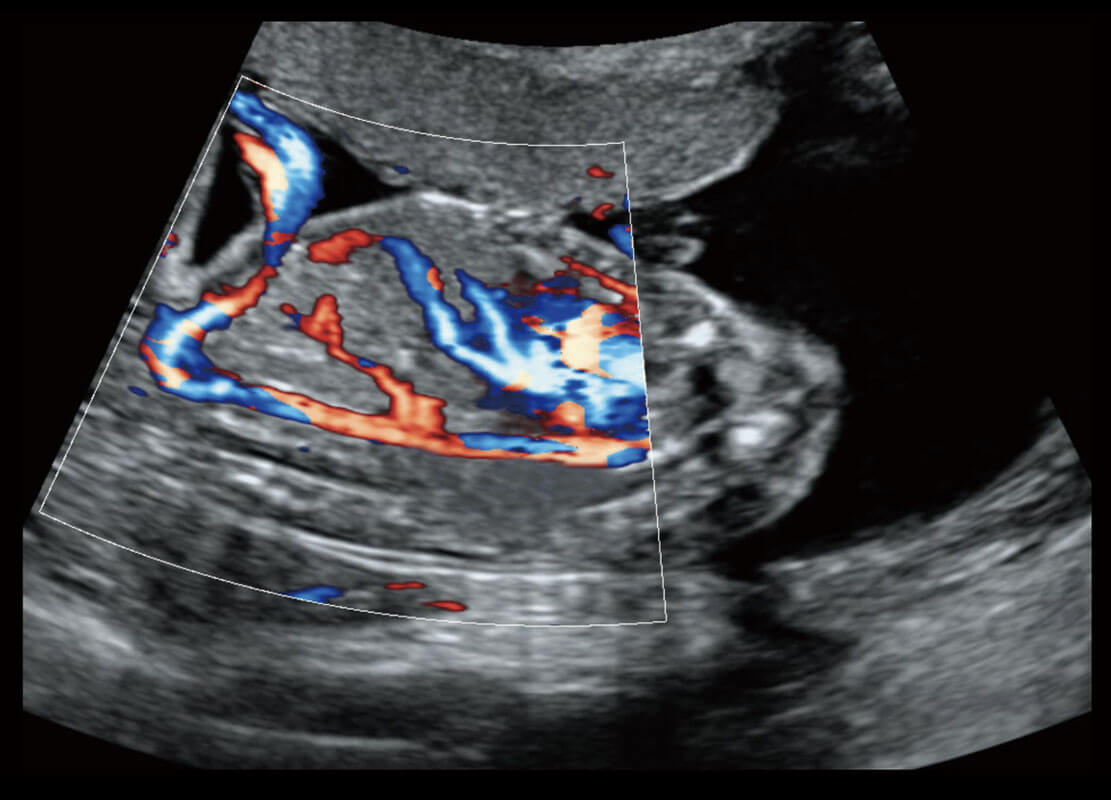

P60搭载一系列胎儿心脏成像技术,实现精细的胎儿心脏评估。

胎心容积成像